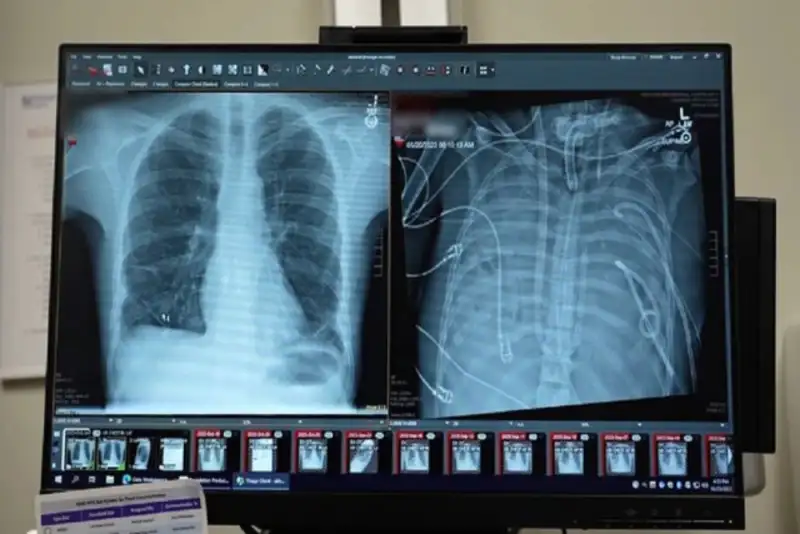

یک مرد 33 ساله با استفاده از سیستم ریه مصنوعی که جریان خون را حفظ می‌کند، به مدت 48 ساعت بدون ریه‌های خود زنده ماند و پس از دریافت پیوند دو ریه، بهبود شگفت‌انگیزی را تجربه کرد.

وضعیت تهدیدکننده حیات

قبل از قرار گرفتن روی سیستم ریه مصنوعی، این مرد دچار سندرم حاد دیسترس تنفسی شده بود که یک وضعیت اغلب تهدیدکننده حیات است که در آن ریه‌ها نمی‌توانند اکسیژن کافی جذب کنند و این مشکل توسط ویروس آنفلوانزا ایجاد شده بود. سپس او روی ونتیلاتور قرار گرفت، اما دچار عفونت مقاوم به دارو شد. این عفونت باعث شد قسمت‌هایی از ریه‌های او پر از چرک شود و او وارد شوک سپتیک شود که در این مرحله قلب و کلیه‌هایش شروع به از کار افتادن کردند.

بهارات می‌گوید: او خیلی بیمار بود، دچار ایست قلبی شد و در حال مرگ بود. از آنجا که این مرد خیلی بیمار بود که پیوند ریه دریافت کند، گروه پزشکان تصمیم گرفتند ریه‌های او را که منبع عفونت بود، بردارند.

بهبود شگفت‌آور

به طور شگفت‌انگیز، مرد شروع به بهبود سریع کرد. در عرض ۴۸ ساعت، او همه داروها برای حمایت از فشار خون را کنار گذاشت، عملکرد کلیه او کاملا بازیابی شد و قلب او به طور طبیعی کار می‌کرد. در این مرحله، مرد پیوند دو ریه را دریافت کرد و سال‌ها بعد هیچ نشانه‌ای از رد عضو یا اختلال عملکرد ریه نشان نداد. اکنون تقریبا سه سال از انجام این کار گذشته است و حال بیمار واقعا خوب است.